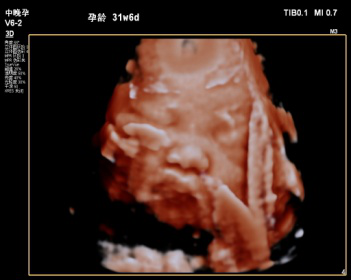

2019年县中医院功能科特引进飞利浦EPIQ5全身高档彩色多普勒超声,配备有心脏、腹部、浅表、腔内及三维容积等5把探头。其专有的purewave纯净波单晶技术,可提高在难以成像的患者身体中的穿透力,使成像更快捷、更清晰;飞利浦EPIQ5在孕期检查中也独具优势,通过图像的切割、旋转及高平面图像的分析,能直观、立体显示胎儿在母体子宫内的立体形态、表面特征、空间位置关系,尤其胎儿面部的三维成像,清晰、直观,准爸爸、准妈妈可以通过屏幕亲眼目睹胎儿的眼睛、嘴巴、鼻子和脸颊,甚至可以看到宝宝在妈妈肚子里运动、呼吸、吞咽、打哈欠、伸舌头等生理活动,非常直观。

每个孕妈妈都希望生个健康的宝宝,因此一定不要忘记这项重要的超声检查哦,不然错过时间可没有办法弥补了。我科室现已正式开展三维彩超,看这些可爱的宝宝!